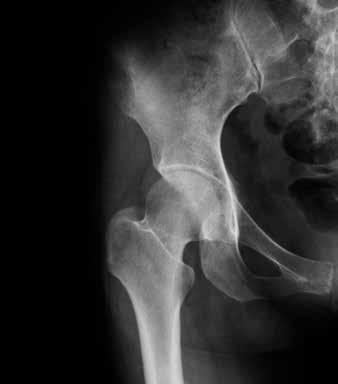

Die Diagnose einer Arthrose erfolgt mittels Anamnese (systematische Befragung zum Gesundheitszustand), körperlicher Untersuchung sowie Ausschluss anderer Erkrankungen durch eine ärztliche Fachperson. Unterstützend werden Röntgenaufnahmen gemacht, um Ausprägung und Schweregrad in den betroffenen Gelenken zu ermit-

teln. Im Gegensatz zur entzündlichen Rheumatoiden Arthritis hat die Blut untersuchung bei der Diagnosestellung der Arthrose einen untergeordneten Stellenwert. Sie kommt ins Spiel vor allem bei Mangel zuständen oder Stoff wechselstörungen.

Gesundes Hüftgelenk Arthrotisches Hüftgelenk

Wie sich die Arthrose im Laufe der Zeit entwickelt, ist von Person zu Person ganz unterschiedlich. Es können ein oder mehrere Gelenke davon betroffen sein. Ob jemand mit Schmerzen, Steifheit und Bewegungseinschränkungen rechnen muss, ist im Anfangsstadium nicht vorauszusehen. Manchmal sind auf der Röntgenaufnahme starke Veränderungen sichtbar, der Betroffene merkt jedoch kaum etwas davon im täglichen Leben. Umgekehrt sind heftige Schmerzen möglich, ohne dass im Röntgenbild ein ausgeprägter Knorpelabbau sichtbar ist.